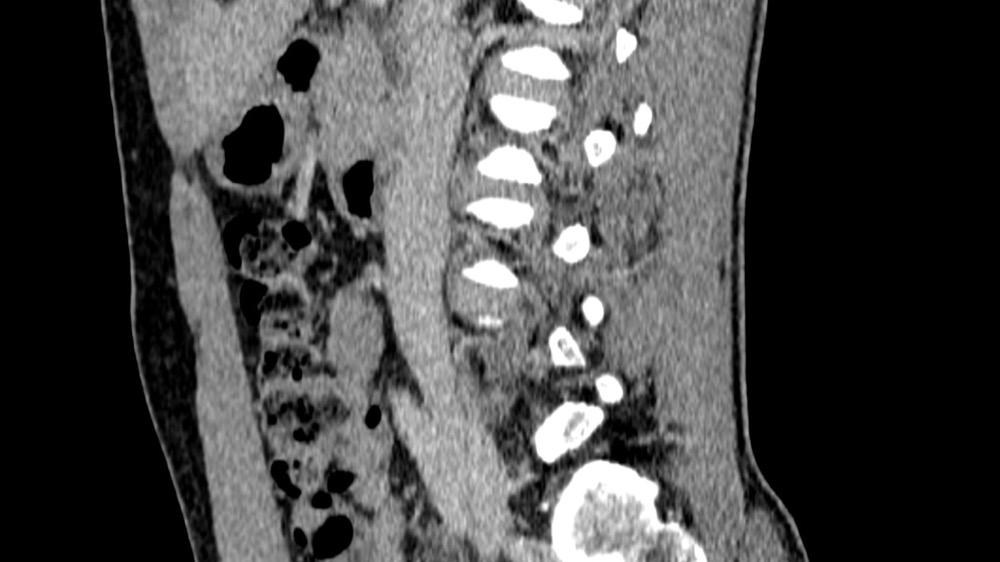

Constance du Boisbaudry 19/01/2022